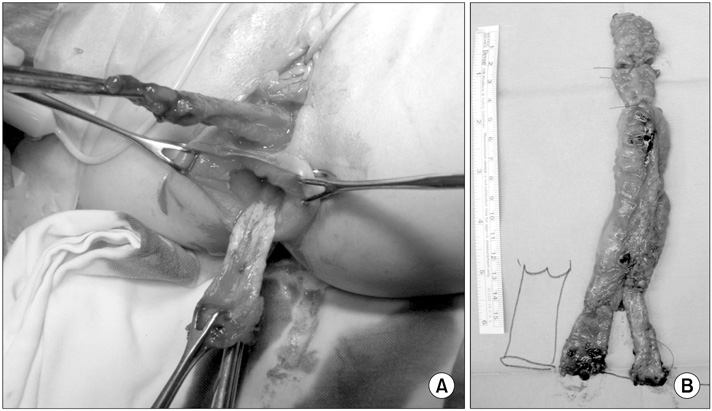

Fig. 3), complete resection of both the anterior duplicated bowel and posterior native bowel up to the merging point with colo-anal anastomosis was performed (

Fig. 4).

Fig. 5 shows a schematic diagram of surgical findings. Pathologic examination confirmed a duplicated colonic segment with a common proper muscle layer. The patient was discharged on the 8th postoperative day without incident. During a 3-year follow-up, she defecated normally without complications.

Fig. 4Operative findings. (A) The tubular anorectocolonic duplication and the normal anorectum were dissected from neighboring structures. (B) Resected specimen.